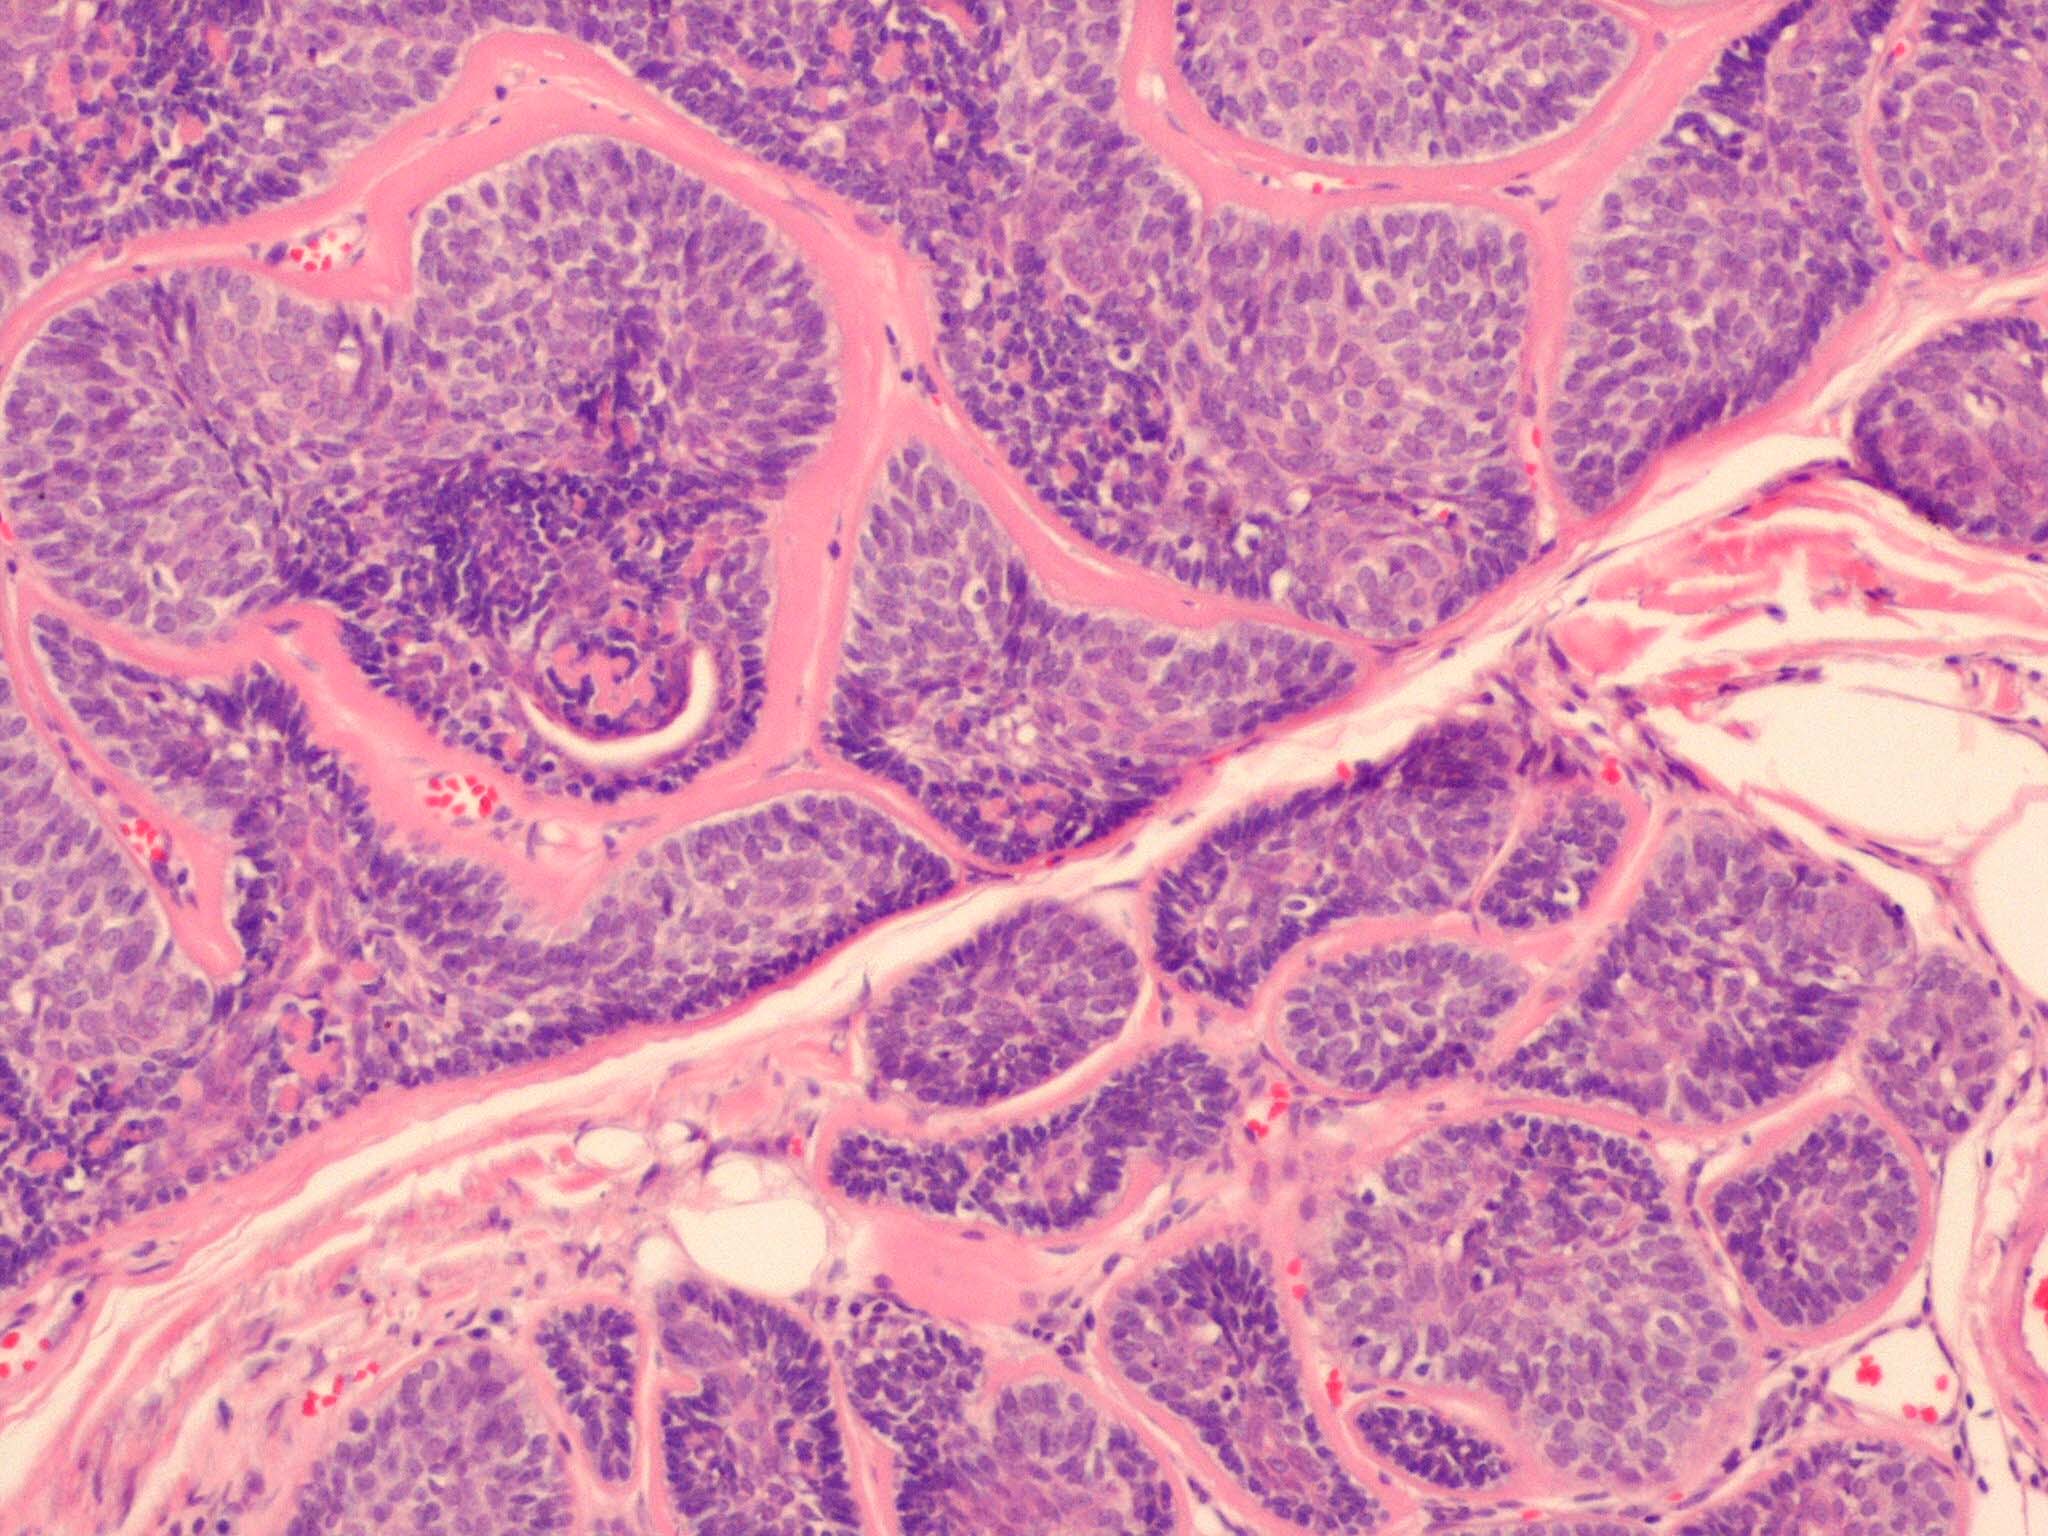

Cylindroma =الأسطوانوم

OLYMPUS DIGITAL CAMERA